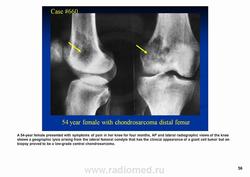

Рентгенологически выявляют в очаге деструкции участки обызвествления в виде крапчатости; кортикальный слой с признаками эрозии со стороны эндоста и истончения; размеры опухоли более 4 см; периостальная реакция слабо выражена или отсутствует; может наблюдаться деструкция кортикальной кости и наличие мягкотканного компонента; в длинных костях локализуется чаще в метафизах и диафизах; интенсивное внутрикостномозговое распространение.